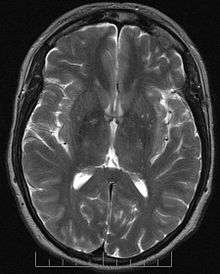

The MRI sequences used look at the symmetry of brain water diffusion. Bundles of fiber tracts make the water diffuse asymmetrically in a tensor, the major axis parallel to the direction of the fibers. The asymmetry here is called anisotropy. There is a direct relationship between the number of fibers and the degree of anisotropy.

Tractography is performed using data from diffusion tensor imaging. Diffusion MRI, a method to produce images of the molecular diffusion process in tissues, was introduced in 1985, notably for its potential for neuroimaging.[4][5] An improvement of diffusion MRI, called Diffusion Tensor MRI or DTI [6][7] allows to fully characterize molecular diffusion in the 3 dimensions of space. Free diffusion occurs equally in all directions. This is termed "isotropic" diffusion. If the water diffuses in a medium with barriers, the diffusion will be uneven, which is termed "anisotropic" diffusion. In such a case, the relative mobility of the molecules from the origin has a shape different from a sphere. This shape is often modeled as an ellipsoid, and the technique is then called diffusion tensor imaging. Barriers can be many things—cell membranes, axons, myelin, etc.; but in white matter the principal barrier is the myelin sheath of axons. Bundles of axons provide a barrier to perpendicular diffusion and a path for parallel diffusion along the orientation of the fibers.

Anisotropic diffusion is expected to be increased in areas of high mature axonal order. Conditions where the myelin or the structure of the axon are disrupted, such as trauma, tumors, and inflammation reduce anisotropy, as the barriers are affected by destruction or disorganization.

Anisotropy is measured in several ways. One way is by a ratio called "fractional anisotropy" (FA). An anisotropy of "0" corresponds to a perfect sphere, whereas 1 is an ideal linear diffusion. Well-defined tracts have FA larger than 0.20. Few regions have FA larger than 0.90. The number gives information of how aspherical the diffusion is but says nothing of the direction.

Each anisotropy is linked to an orientation of the predominant axis (predominant direction of the diffusion). Post-processing programs are able to extract this directional information.

This additional information is difficult to represent on 2D grey-scaled images. To overcome this problem a color code is introduced . Basic colors can tell the observer how the fibers are oriented in a 3D-coordinate system: This is termed an "anisotropic map". The software could encode the colors in this way:

- Red indicates directions in the X axis: right to left or left to right.

- Green indicates directions in the Y axis: posterior to anterior or from anterior to posterior.

- Blue indicates directions in the Z axis: foot-to-head direction or vice versa

Notice that the technique is unable to discriminate the "positive" or "negative" direction in the same axis.